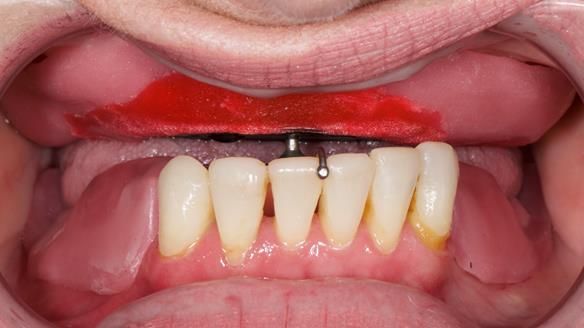

Bad dental experiences over 20 years ago had put Jo off from visiting the dentist. She had resorted to replacing her missing upper front teeth by making a partial denture using artificial teeth and a base made from artificial acrylic nail powder/liquid kit, purchased on the internet. She had recently explored the possibility of immediate load dental implant supported teeth.

- The missing upper front teeth are replaced by a denture made by the patient. This has poor fit and appearance.

- The upper ridge with missing teeth has very little underlying bone.

- The upper natural teeth have hopeless prognosis due to dental caries.

- The forces placed on the teeth are large (bruxism). This will make the dentures proposed in the treatment plan below wear, chip and break more quickly. Therefore, the final dentures will require metal reinforcement to make them as robust as possible.

The clinical situation and treatment process is shown in detail below. I provided the clinical work. Rowan Garstang provided the technical work. This treatment took 25 visits over a period of 12 months.